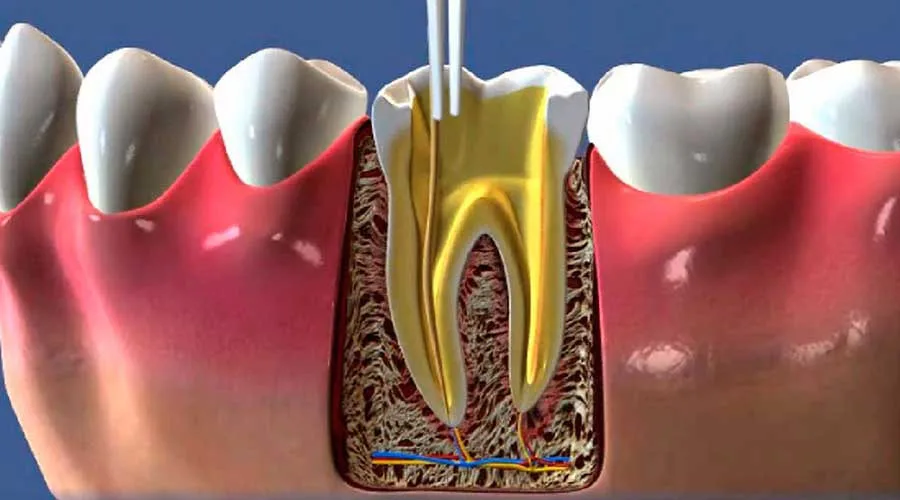

O foco do atendimento especializado é remover o foco infeccioso sem a necessidade de extração. Através de protocolos rigorosos, o especialista limpa e sela os canais radiculares, devolvendo a funcionalidade mastigatória e o bem-estar sistêmico ao paciente.

Tratamento de Canal: Remoção da polpa inflamada com total precisão técnica;

Sessão de Tratamento: Procedimento realizado sob anestesia local, priorizando o conforto total;